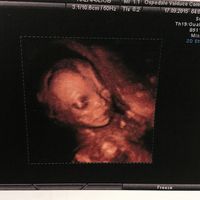

Foto 3d/4d del vostro bimbo/a!

Lena in Future mamme, Il 30 Ottobre 2015 alle 16:37

Ho una sola foto del mio bimbo in 4D (quella della morfologica) e la tengo sul cellulare per riguardarla ogni volta che voglio. I primissimi giorni dopo l'eco la guardavo almeno 10 volte al giorno, mi...

Olimpia, venerdì 6-Nov-15 4 378